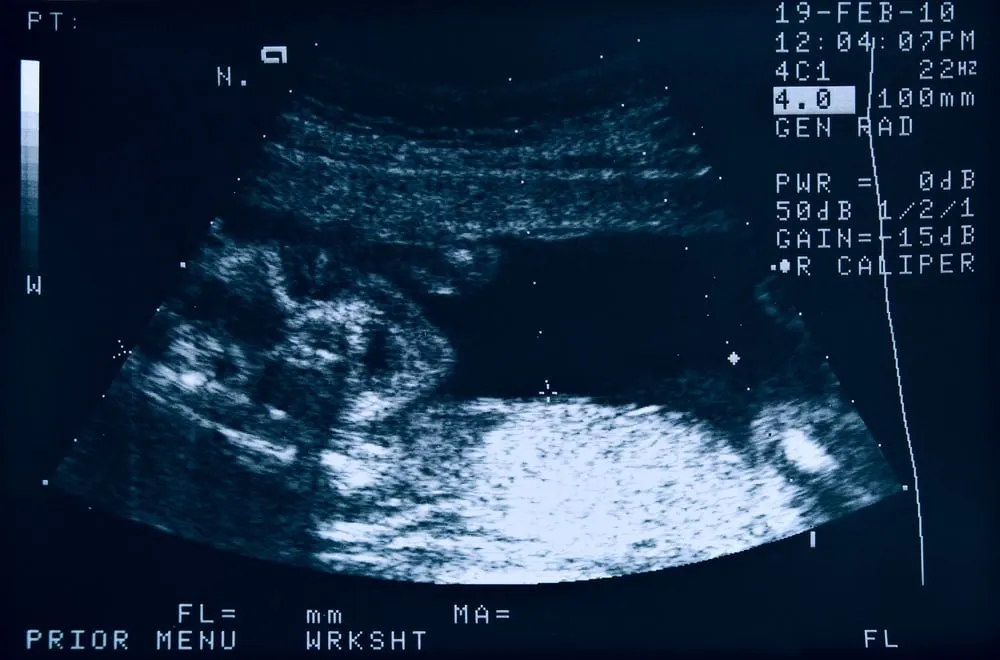

- Siêu âm 4D, 5D kết hợp đo các chỉ số phát triển của thai nhi

- Siêu âm thai, các bác sĩ có thể kiểm tra cân nặng, kích thước và các chỉ số của thai nhi 22 tuần tuổi